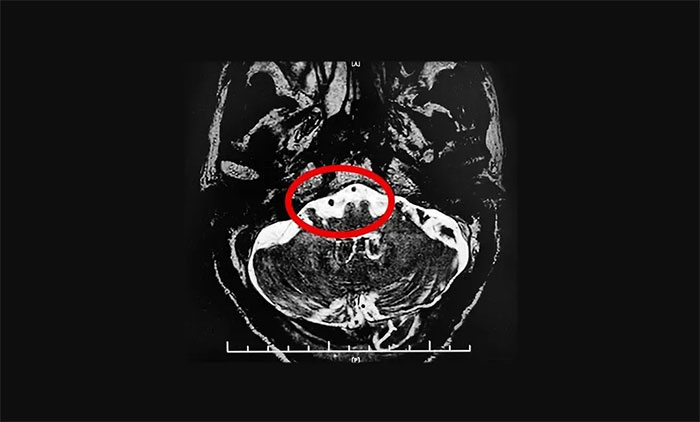

▲雙側(cè)三叉神經(jīng)與周圍小血管關(guān)系密切(左側(cè)接觸顯著)

在辦理入院手續(xù)后,楊忠旭教授詳細(xì)了解了張老漢的病史資料,并為其申請了三叉神經(jīng)MRTA平掃+增強(qiáng)等相關(guān)檢查。結(jié)合影像資料,楊忠旭教授指出患者雙側(cè)三叉神經(jīng)與周圍小血管關(guān)系密切(左側(cè)接觸顯著),手術(shù)指征明顯,未見明顯手術(shù)禁忌癥。